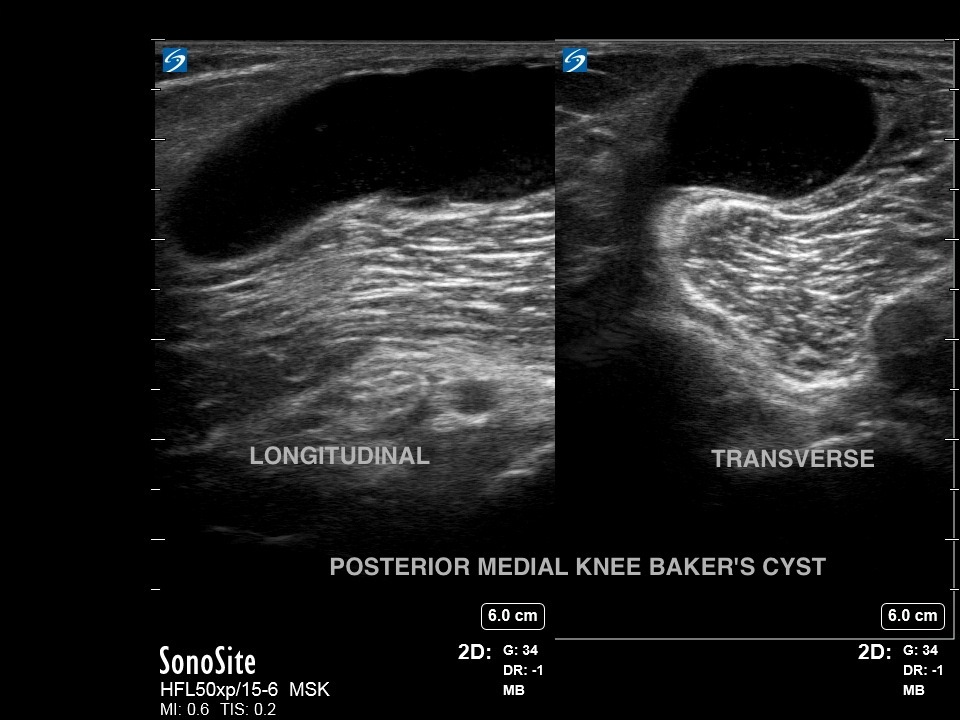

膝部贝克氏囊肿双图像